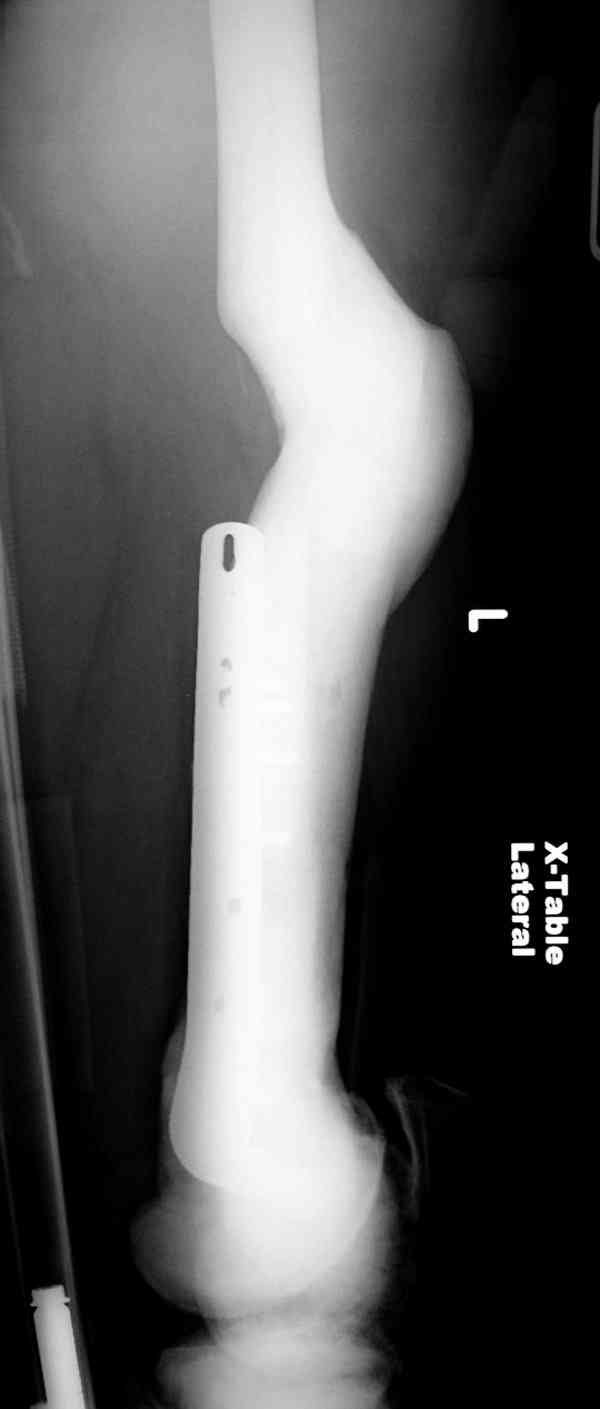

“При лечении переломов у больных с остеопетрозом (в прошлом году был случай) необходимо быть готовым к длительным операциям из-за трудности

обработки традиционными методами "мраморной" кости, иметь в наличие достаточное количество свежих острых инстументов и персонала при необходимости замены (были случаи отстрочки операции на следующий день из-за физической усталости персонала), и надо избежать особо трудоемких операции как интрамедуллярное сверление”.

Не являюсь специалистом по костной патологии, но мне кажется, на ренгенограмме множественные мета-диафизарные образования напоминяющее змееподобных извилистых линии и периостеальные ламинирование очень напоминяет картину остеонекроза (инфаркта) костей, возможно связано с длительным применением стероидов.

При предоставлении дополнительных информации, сканнирования, МРТ и лабараторных данных можно уточнить предварительный диагноз, пока склонен к обширному костному инфаркту, и таких больных рекомендуем лечить сиптоматически.

слайды из прошлегодного случая.